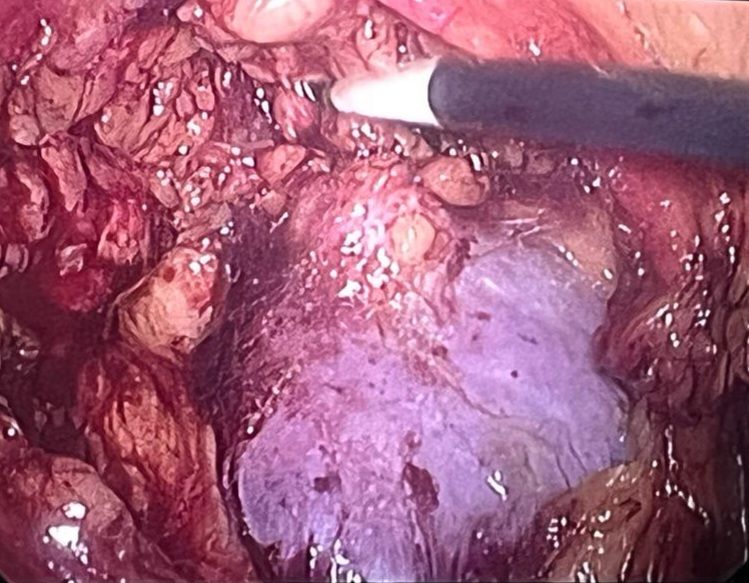

Gracias a la incorporación de técnicas avanzadas, como las cistoscopias flexibles, microcirugías, litotricia láser y laparoscopia, puedo asegurar que cada procedimiento se realiza de manera mínimamente invasiva, lo que permite una recuperación más rápida y menos dolorosa. Estos avances tecnológicos no solo mejoran la precisión de los diagnósticos, sino que también optimizan el tratamiento, minimizando riesgos y favoreciendo el bienestar de mis pacientes.